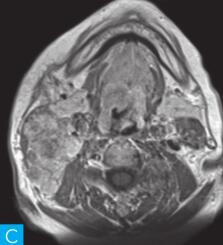

图1 咽喉部MRI:A.喉咽部MR横断面平扫T1WI;B.喉咽部MR横断面T2WI;C.喉咽部MR横断面T2压脂;D.喉咽部MR横断面增强T1WI;E.喉咽部MR冠状面T2WI;F.咽喉部MR冠状面增强T1WI

MRI平扫可见右侧扁桃体较大的软组织肿块,T1WI呈稍低信号,T2WI呈稍高信号,信号较均匀,T2WI压脂序列上呈高信号,病变与右侧咽扁桃体及舌根部分界不清,左侧咽扁桃体肿大,口咽腔明显变形狭窄,病灶延伸至喉前庭;双侧锁骨上窝及颈血管鞘周围间隙内可见多发大小不等的肿大淋巴结,大部分肿大淋巴结信号较均匀,呈稍高信号,边界清楚,右侧颈部间隙内个别肿大淋巴结内见少量斑片状液化坏死区;增强扫描后下咽部病变及双侧颈部间隙内的肿大淋巴结均呈明显的较均匀强化,提示该两处占位病变的血供较为丰富,且可能为同源性病变,因此采取“一元论”诊断思维进行分析更为合理。

(1)发现病变与认证:扁桃体及颈部病变较为容易发现,主要是分析两方面:一是仔细观察咽部有无原发病变,原发病变的形态及信号;二是评价淋巴结的分布,淋巴结的信号及生长特点。本病例基本征象为扁桃体病变信号均匀,无坏死,颈部淋巴结分布广泛,信号均匀。

(2)定位诊断:对于本病例来说,发现两处病变,包括咽部和颈部。咽部的病变位于扁桃体,延伸至喉咽腔,口咽腔和梨状窝受压变窄。颈部的病变为多发淋巴结增大,淋巴结广泛分布于Ⅱ~Ⅴ区。

本病例的特点为右侧扁桃体肿块,病变边界较清楚,表面光滑,信号均匀。双侧颈部间隙内多发肿大淋巴结,淋巴结围绕颈动脉鞘,部分病变融合倾向,广泛分布于Ⅱ~Ⅴ区,增强后病变较明显强化。

该病例首先对病变进行定位,包括咽部的和颈部的。咽部的病变:病变位于扁桃体,延伸至喉咽腔,口咽腔和梨状窝受压变窄(引起异物感和吞咽困难的原因)。颈部的病变:多发淋巴结增大,淋巴结广泛分布于Ⅱ~Ⅴ区。扁桃体病变的信号特征:扁桃体病变表面光滑,提示黏膜完整,病变来源于黏膜下,病变信号均匀,无坏死,进一步支持病变来源于黏膜下。颈部淋巴结病变的特征:淋巴结分布广泛,信号均匀(可以初步排除结核和转移,后两者容易坏死),围绕颈动脉鞘,但是不侵犯颈动脉鞘(转移容易侵犯颈动脉鞘),部分淋巴结融合倾向(结核淋巴结增大,无融合倾向,而且容易坏死),病变中度强化,进一步支持颈部淋巴瘤的诊断。诊断原则:首先仔细观察咽部有无原发病变,原发病变的形态及信号,尤其黏膜是否完整。其次评价淋巴结的分布,淋巴结的信号及生长特点。